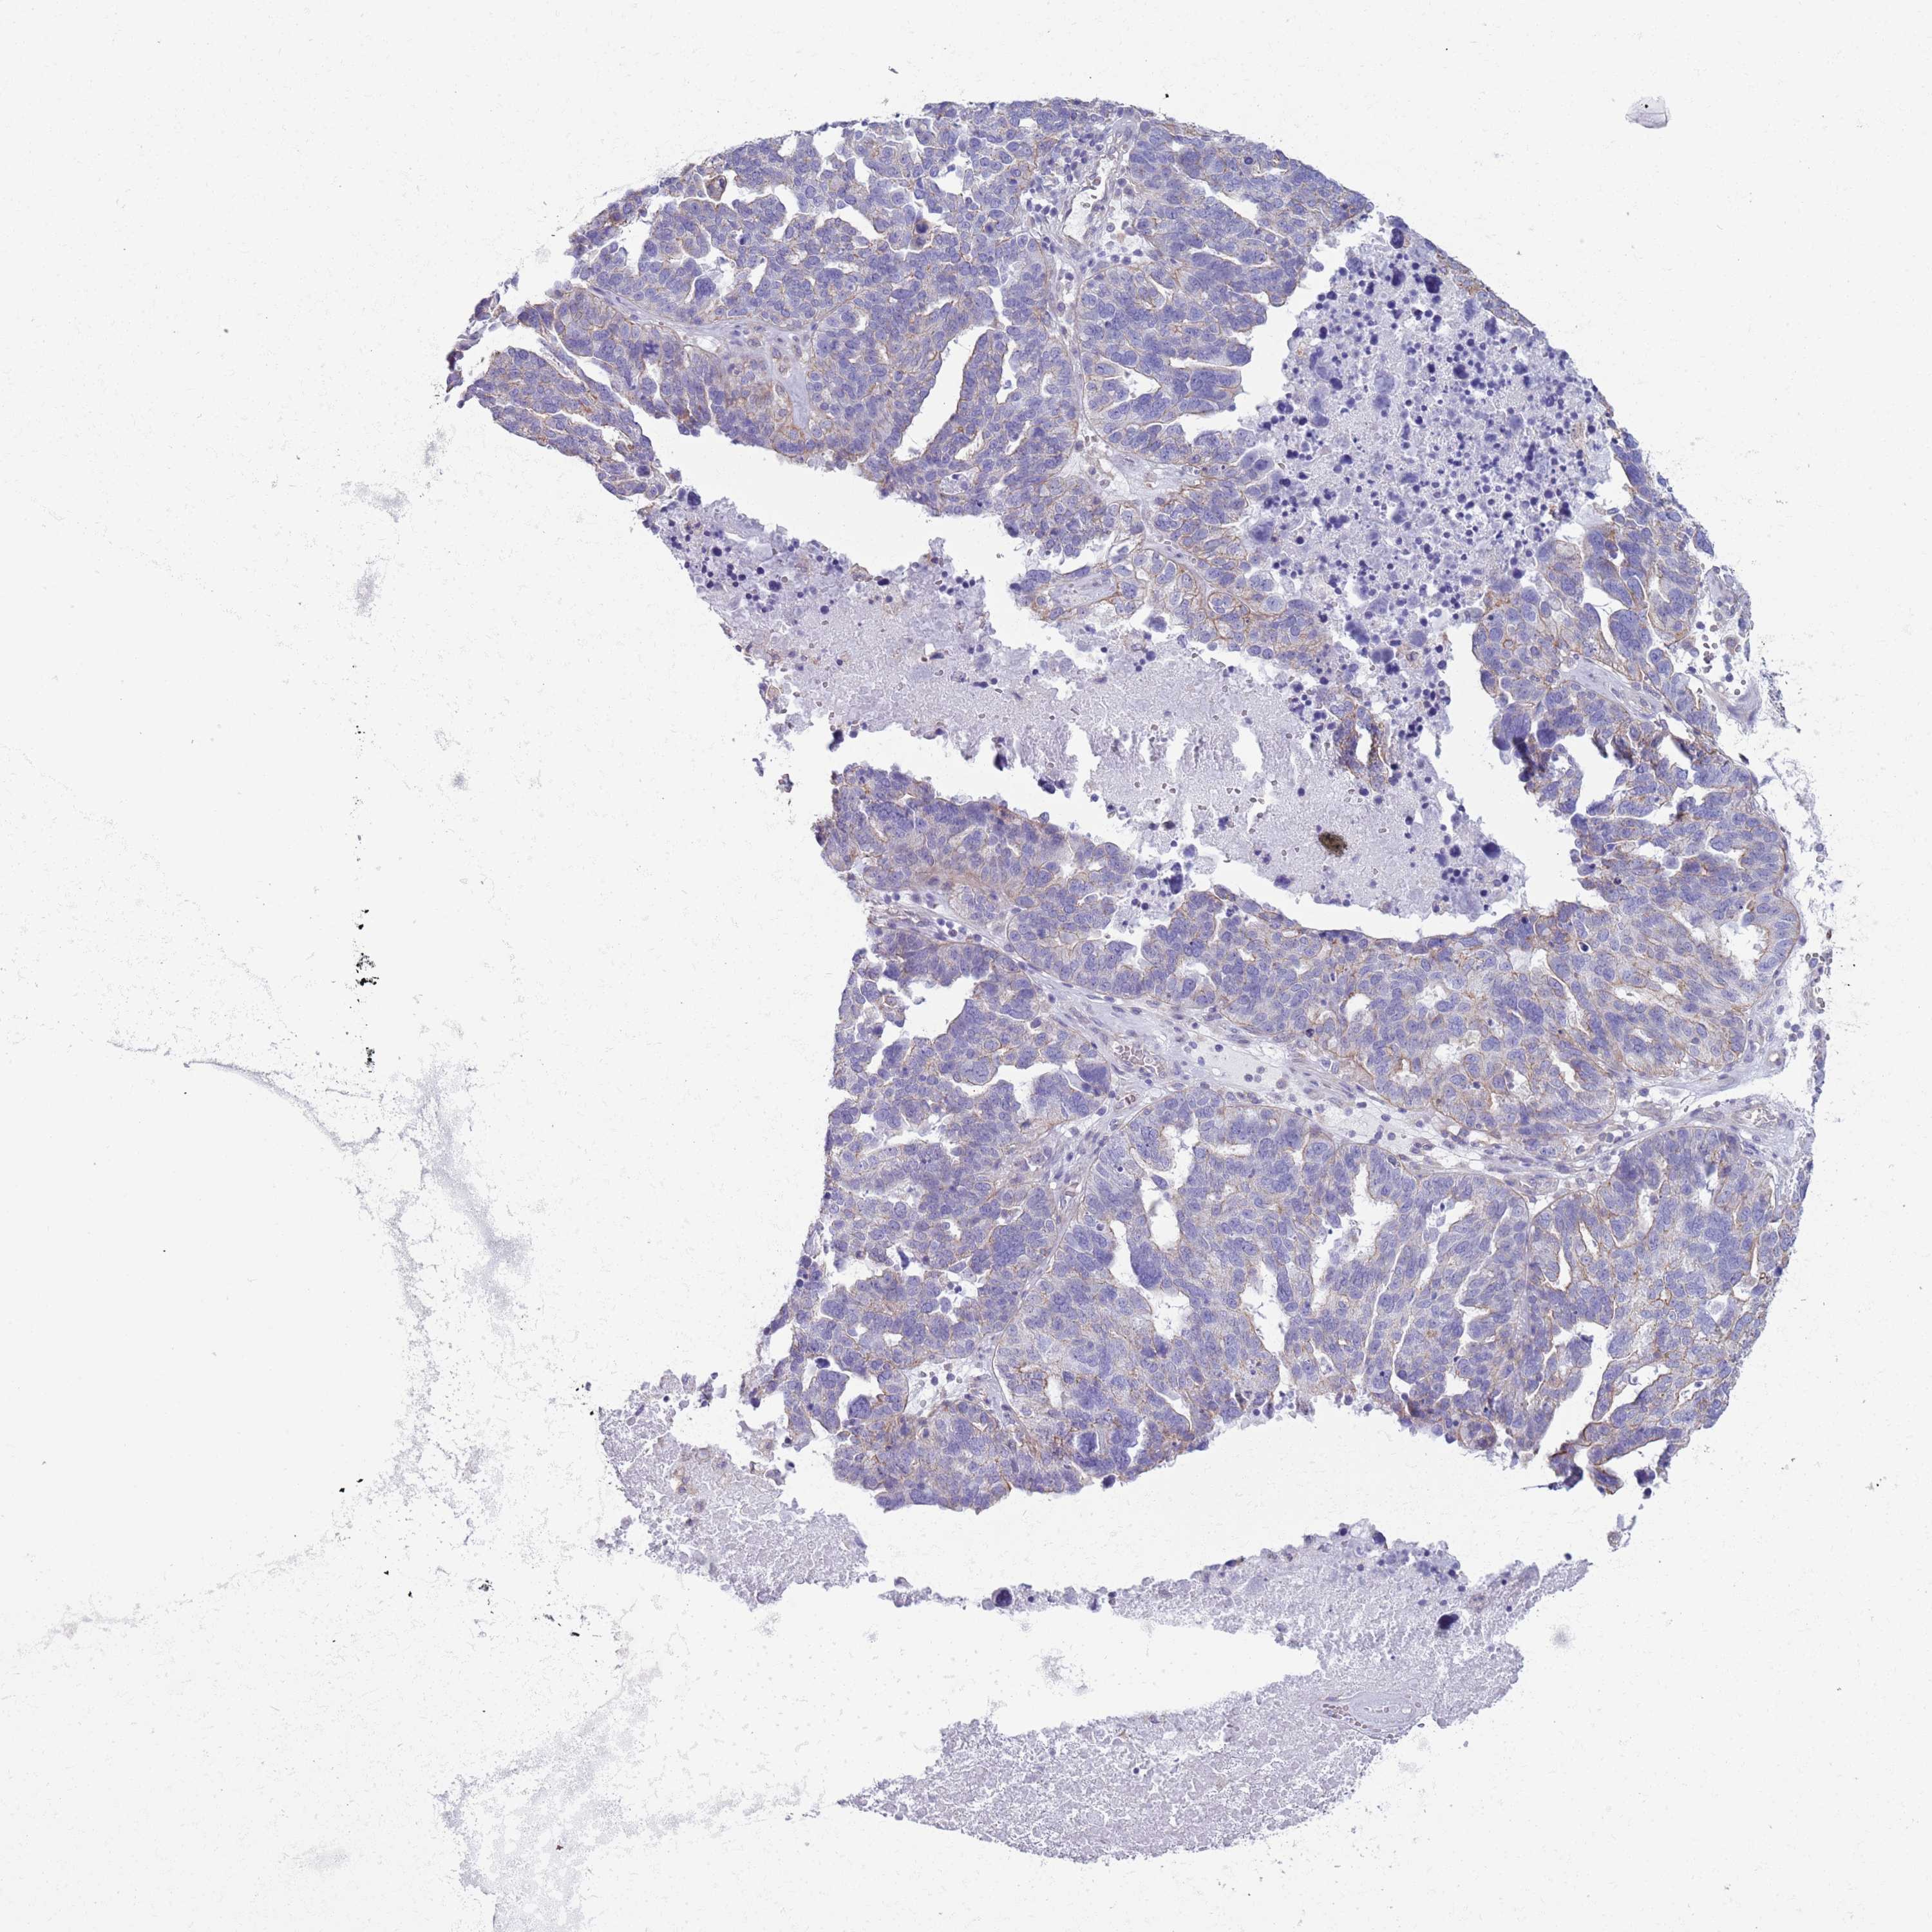

OVARIAN CANCER - Protein expressioni

A mouse-over function shows sample information and annotation data. Click on an image to view it in a full screen mode. Samples can be filtered based on level of antibody staining by selecting one or several of the following categories: high, medium, low and not detected. The assay and annotation is described here.

Note that samples used for immunohistochemistry by the Human Protein Atlas do not correspond to samples in the TCGA dataset.

Antibody stainingi

Antibody staining in the annotated cell types in the current human tissue is reported as not detected, low, medium, or high, based on conventional immunohistochemistry profiling in selected tissues. This score is based on the combination of the staining intensity and fraction of stained cells.

Each image is clickable and will lead to virtual microscopy that enables deeper exploration of all samples and also displays staining intensity scores, fraction scores and subcellular localization as well as patient and tissue information for each sample.

Antibody HPA041301

Antibody HPA044239

Staining

High

Medium

Low

Not detected

Intensity

Strong

Moderate

Weak

Negative

Quantity

>75%

75%-25%

<25%

None

Location

Nuclear

Cytoplasmic/membranous

Cytoplasmic/membranous,nuclear

Cystadenocarcinoma, serous, NOS

Carcinoma, endometroid

Cystadenocarcinoma, mucinous, NOS

Carcinoma, NOS